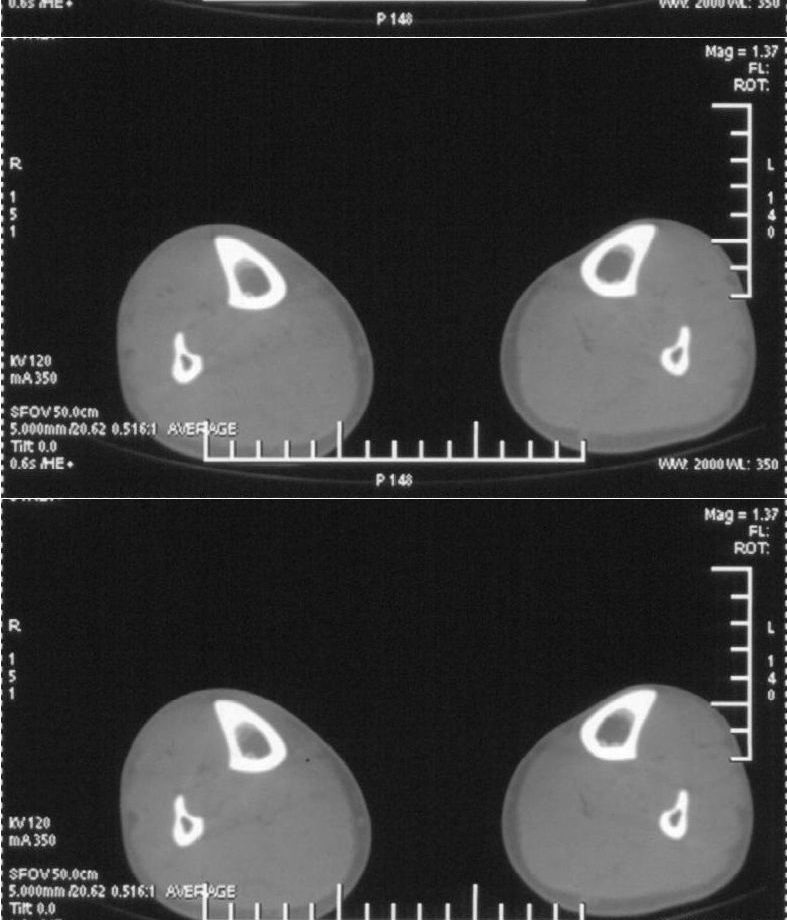

男,42岁。4个月前钢筋钝伤右侧小腿部,当时因无明显外伤,未引起重视。一周后因受伤腿部疼痛,发现肿胀,随后到当地医院进行检查(2008年4月16日)。因未发现骨质异常未引起重视,仅仅进行口服抗生素治疗处理。经过一段时间治疗但未见明显治疗效果在5月29日又进行x线检查,发现有胫骨密度上段密度增高,又进行抗炎治疗,仍未见效果。又在7月3日进行x线检查,仍然报告有胫骨上端密度增高,并建议ct检查。以下是相关检查结果:

髓腔密度呈絮状增高,胫骨上端内侧可见层状骨膜反应,考虑骨髓炎.

髓腔密度呈絮状增高,胫骨上端内侧可见层状骨膜反应,肌间隙模糊,考虑骨髓炎.

破坏、增生、骨膜反应,考虑骨髓炎